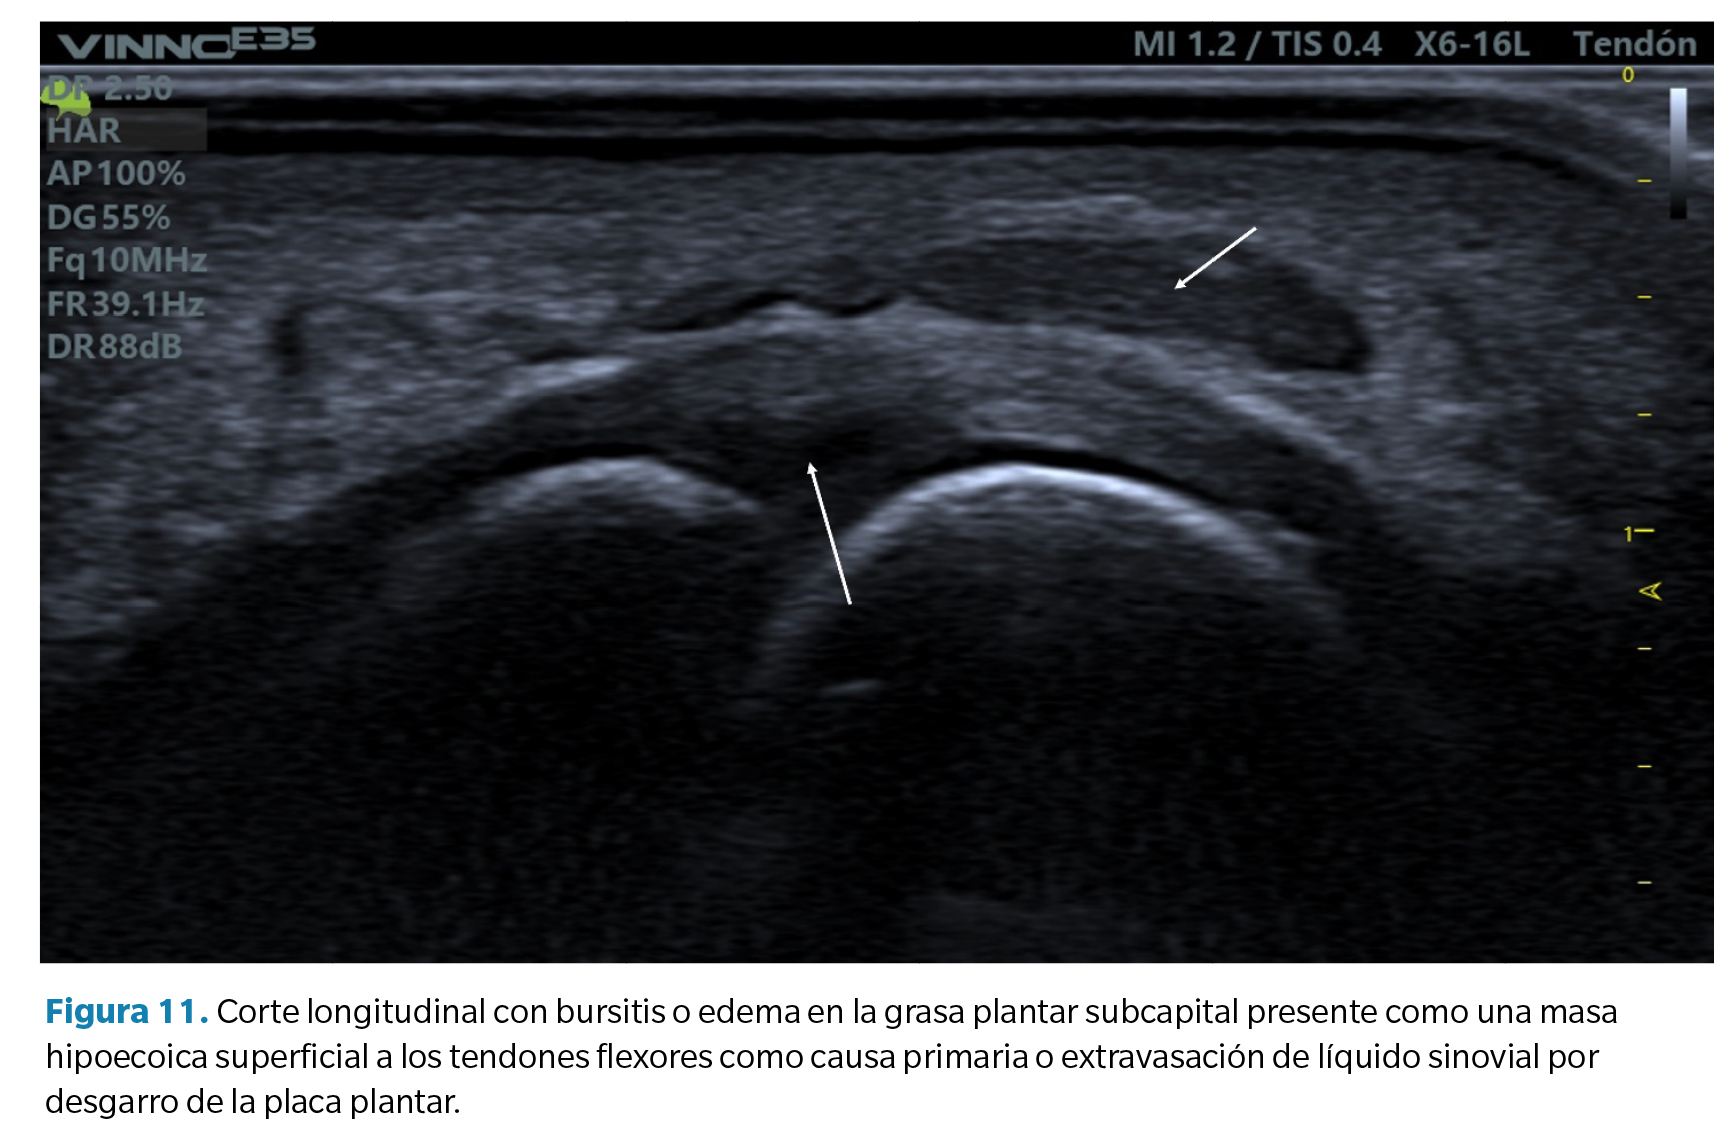

- Bursitis de la grasa plantar. En relación con el hallazgo anterior, algunos casos de desgarros de la placa plantar pueden acompañarse también de un infiltrado hipoecoico en la grasa plantar adyacente. Esto puede ser un defecto primario del exceso de compresión sobre dicha grasa (compresión que también forma parte de la etiología de lesión compresiva de la placa) o bien el resultado de un infiltrado de líquido sinovial por extravasación de la rotura capsular como se ha comentado anteriormente. Es frecuente en estos casos advertir la presencia de un doppler positivo (Figura 11).